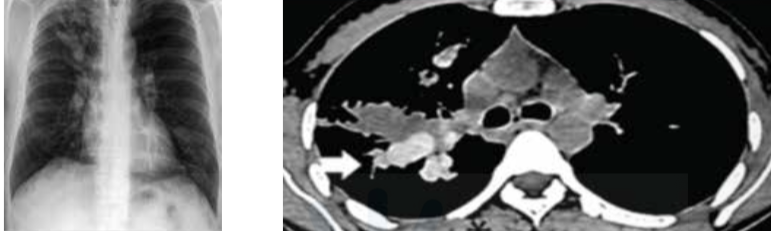

Radiological diagnosis of pleural effusion

Meniscus sign / Ellis S curve